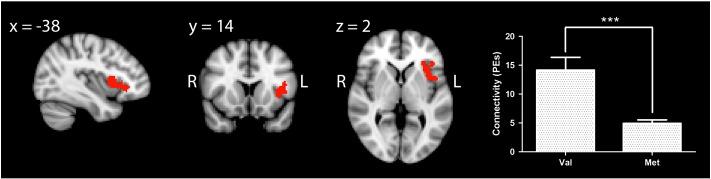

Catechol-O-methyltransferase (COMT) modulates dopamine in the prefrontal cortex (PFC) and influences PFC dopamine-dependent cognitive task performance. A human COMT polymorphism (Val(158)Met) alters enzyme activity and is associated with both the activation and functional connectivity of the PFC during task performance, particularly working memory. Here, we used functional magnetic resonance imaging and a data-driven, independent components analysis (ICA) approach to compare resting state functional connectivity within the executive control network (ECN) between young, male COMT Val(158) (n=27) and Met(158) (n=28) homozygotes. COMT genotype effects on grey matter were assessed using voxel-based morphometry. COMT genotype significantly modulated functional connectivity within the ECN, which included the head of the caudate, and anterior cingulate and frontal cortical regions. Val(158) homozygotes showed greater functional connectivity between a cluster within the left ventrolateral PFC and the rest of the ECN (using a threshold of Z>2.3 and a family-wise error cluster significance level of p<0.05). This difference occurred in the absence of any alterations in grey matter. Our data show that COMT Val(158)Met affects the functional connectivity of the PFC at rest, complementing its prominent role in the activation and functional connectivity of this region during cognitive task performance. The results suggest that genotype-related differences in prefrontal dopaminergic tone result in neuroadaptive changes in basal functional connectivity, potentially including subtle COMT genotype-dependent differences in the relative coupling of task-positive and task-negative regions, which could in turn contribute to its effects on brain activation, connectivity, and behaviour.